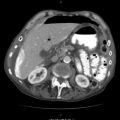

Fig. 29.1

Neck incision through the platysmal layer; then retract the SCM muscle laterally

Once you divide the platysma and retract the SCM laterally, your next objective is to identify the internal jugular (IJ) vein and retract it laterally with a self-retraining blunt retractor. The facial vein usually needs to be ligated and divided to allow the IJ to retract laterally. Often there is a pseudoaneurysm/hematoma encountered at this point; however, if the hematoma remains intact, it is helpful to dissect alongside the hematoma in order to gain control of either proximal or distal vessels. Depending upon the position of the hematoma, you may only be able to obtain control of one or the other prior to invading the pseudoaneurysm. It is unlikely that you will be able to do both prior to opening the hematoma, but if possible certainly gaining both proximal and distal control is ideal. I prefer to gain control with vessel loops vs. vascular clamps in the neck, as the vessel loops are less traumatic to a soft, healthy carotid artery (Fig. 29.2).